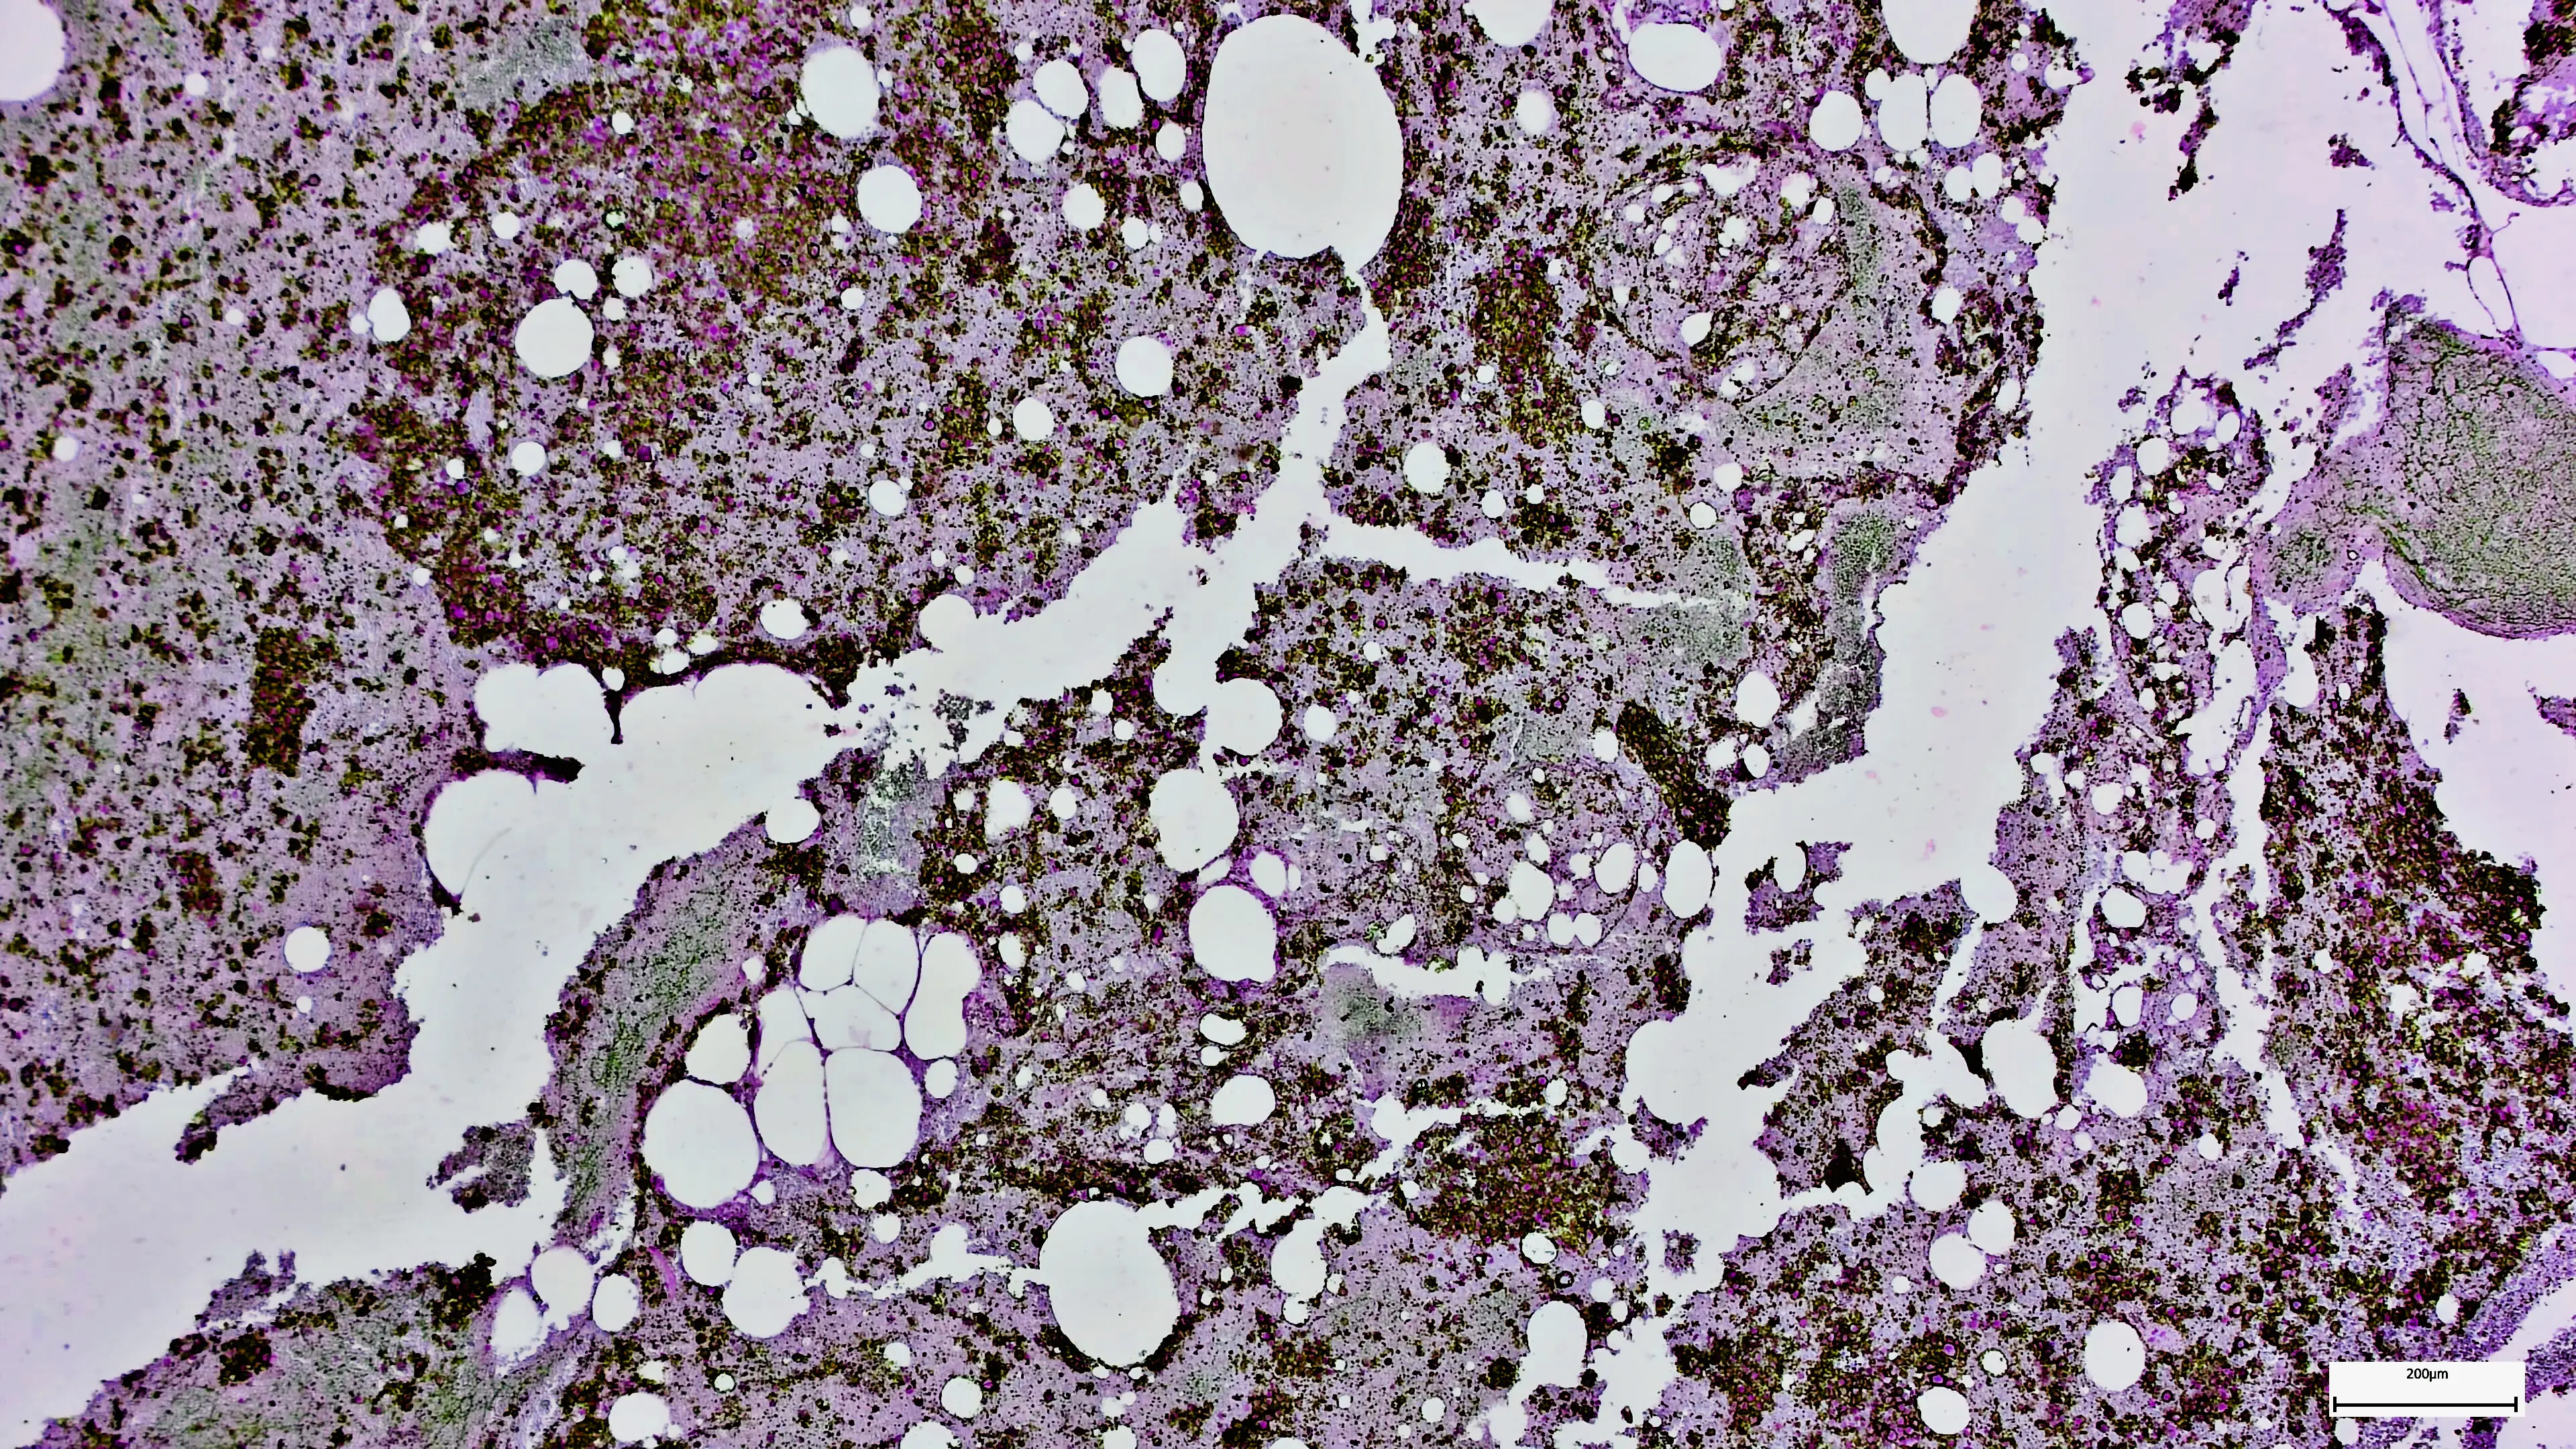

Joint research from University of Southern Denmark and Odense University Hospital analysed the gut bacteria of over 800 people, with half of participants having colon cancer, specifically around the bacterium Bacteroides fragilis.

This led to researchers examining the bacteria itself for differences, finding a previously undescribed virus, named bacteriophage, inside the bacteria of colon cancer patients.